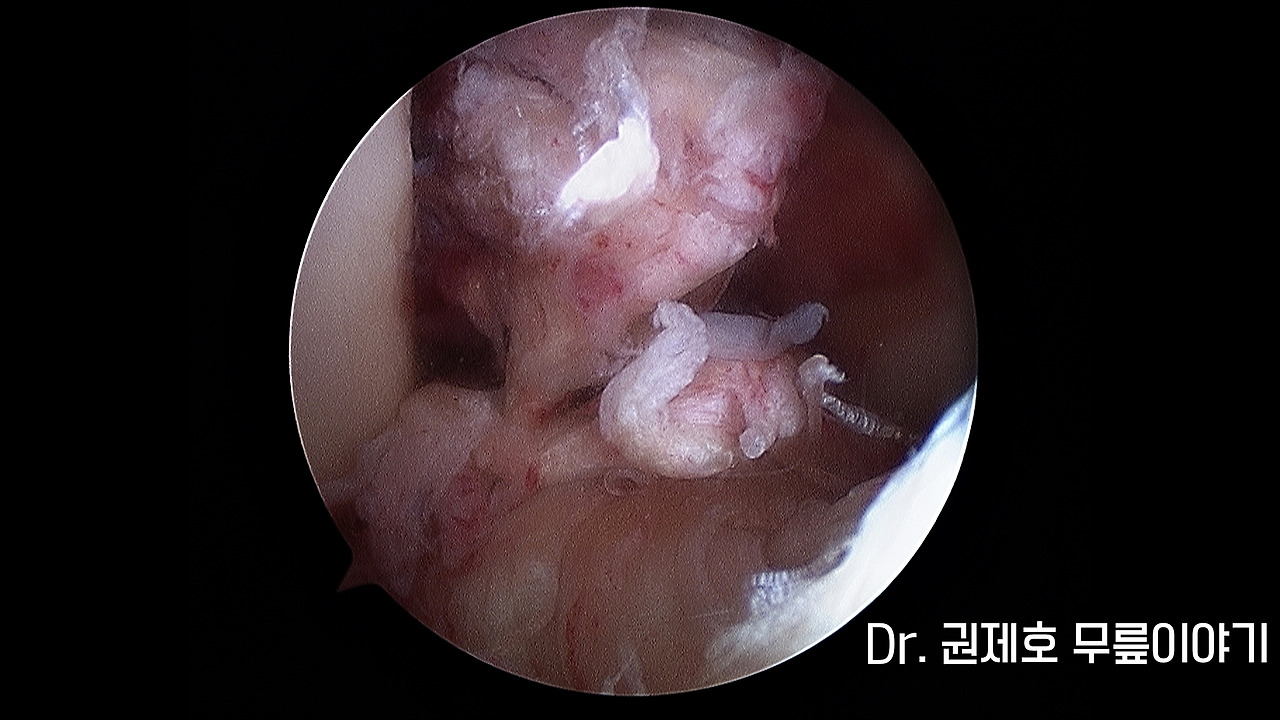

전방십자인대파열 타가건 재건술 (16).jpg 전방 십자인대 파열 모습

무릎 관절경으로 파열된 전방 십자인대를 확인합니다. 사진에서 보면 완전 파열의 형태를 보여주고 있습니다.